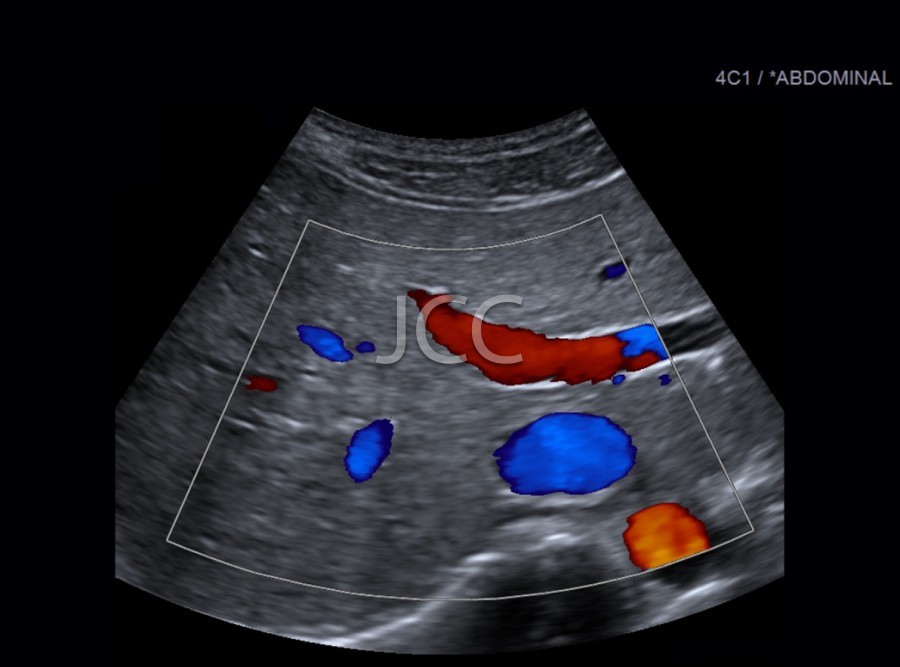

Ecografia - Ecografia Vascular - Doppler

A Ecografia constitui um método mais acessível permitindo de modo simples e rápido a avaliação dos órgãos do corpo humano incluindo o fígado, vias biliares, vesícula, pâncreas, rins, bexiga e próstata, bem como órgãos de menores dimensões como a tiróide, parótidas e estruturas musculares.

Constitui uma óptima técnica para guiar a realização de biópsia. Quando associada ao Doppler permite o estudo das estruturas vasculares arteriais e venosas de modo dinâmico.